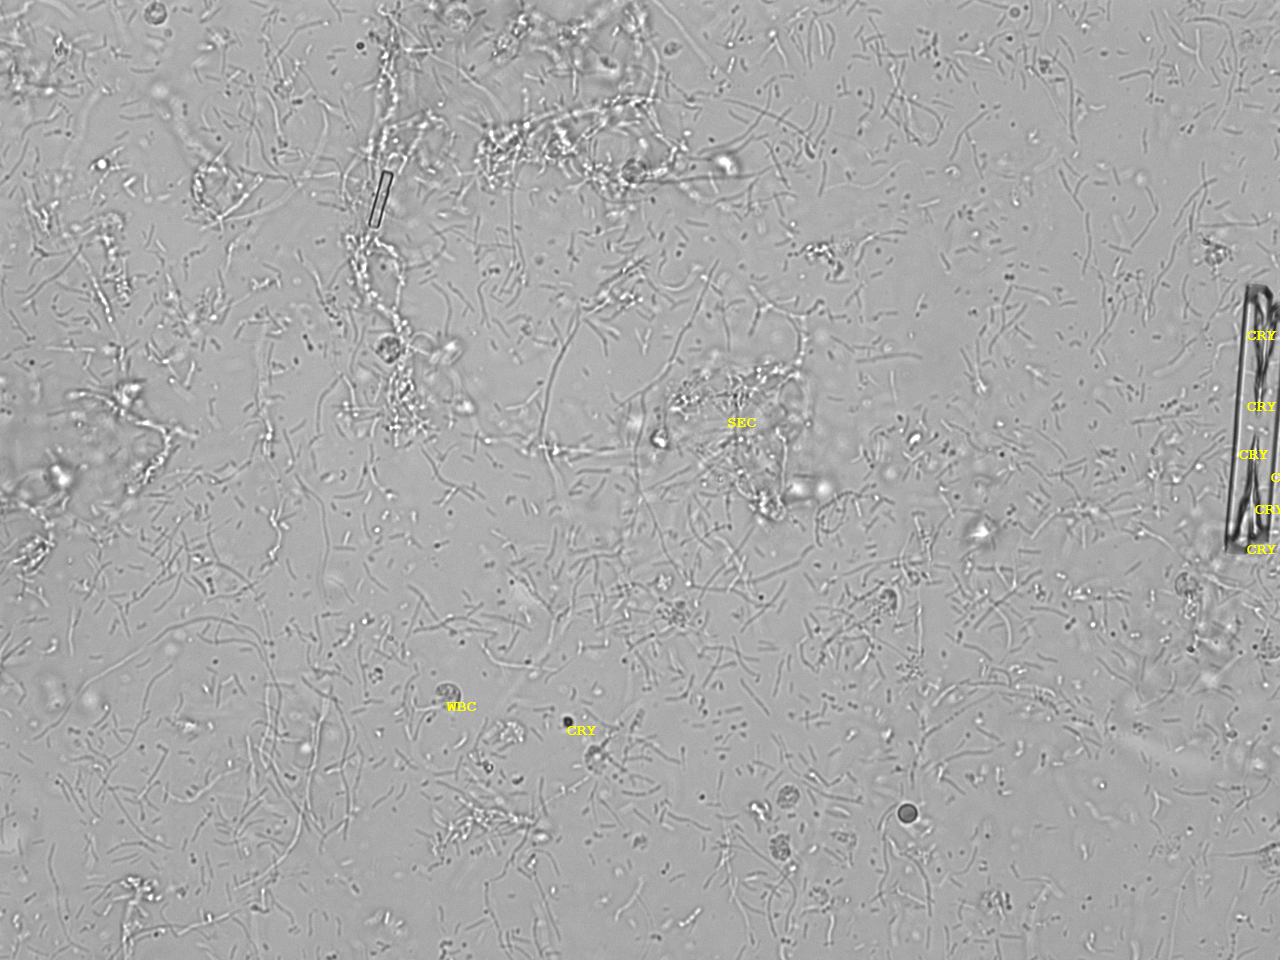

Urin-Feature: CaPhosphate